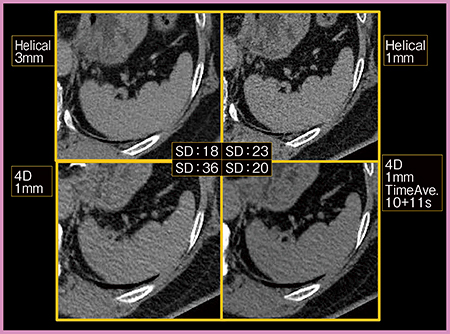

今後は,まず,画像や撮影法の最適化と,さらなる被ばく低減が課題となる。Dynamic Volume Scanでは被ばくを考慮して撮影するため,ヘリカルCTと比べ画質が低下するが,Time Average法を用いて2回転分のデータを1画像とすることで,ヘリカルCTと遜色ない画質を得ることができる(図8)。

図8 320列ADCTの画質向上